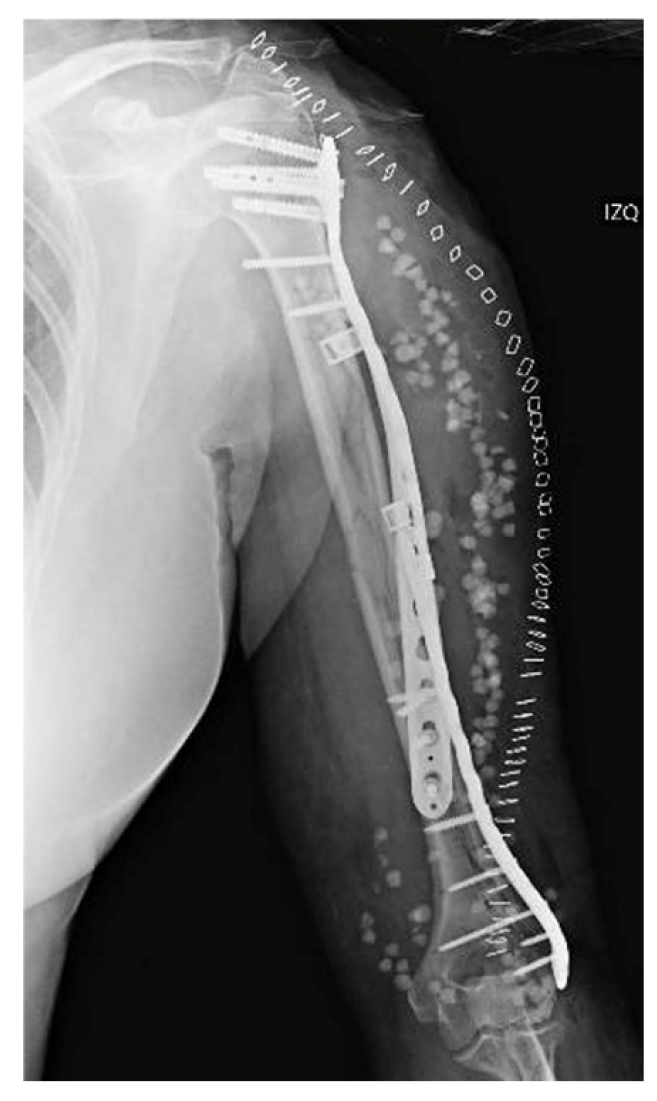

This is the case of a 62-year-old female who was admitted to our hospital following an accidental fall down the stairs that resulted in trauma to her (non-dominant) left upper limb. The patient had a history of ischemic heart disease, and her physical examination revealing pain, deformity and functional disability in the arm. A distal neurovascular examination detected no abnormalities. The radiological examination revealed an AO 12B2 segmental spiral fracture in the proximal third of the humeral shaft [4] (Figure 1).

Figure 1. X-ray of the initial injury, showing a proximal humerus fracture extending into the diaphysis.